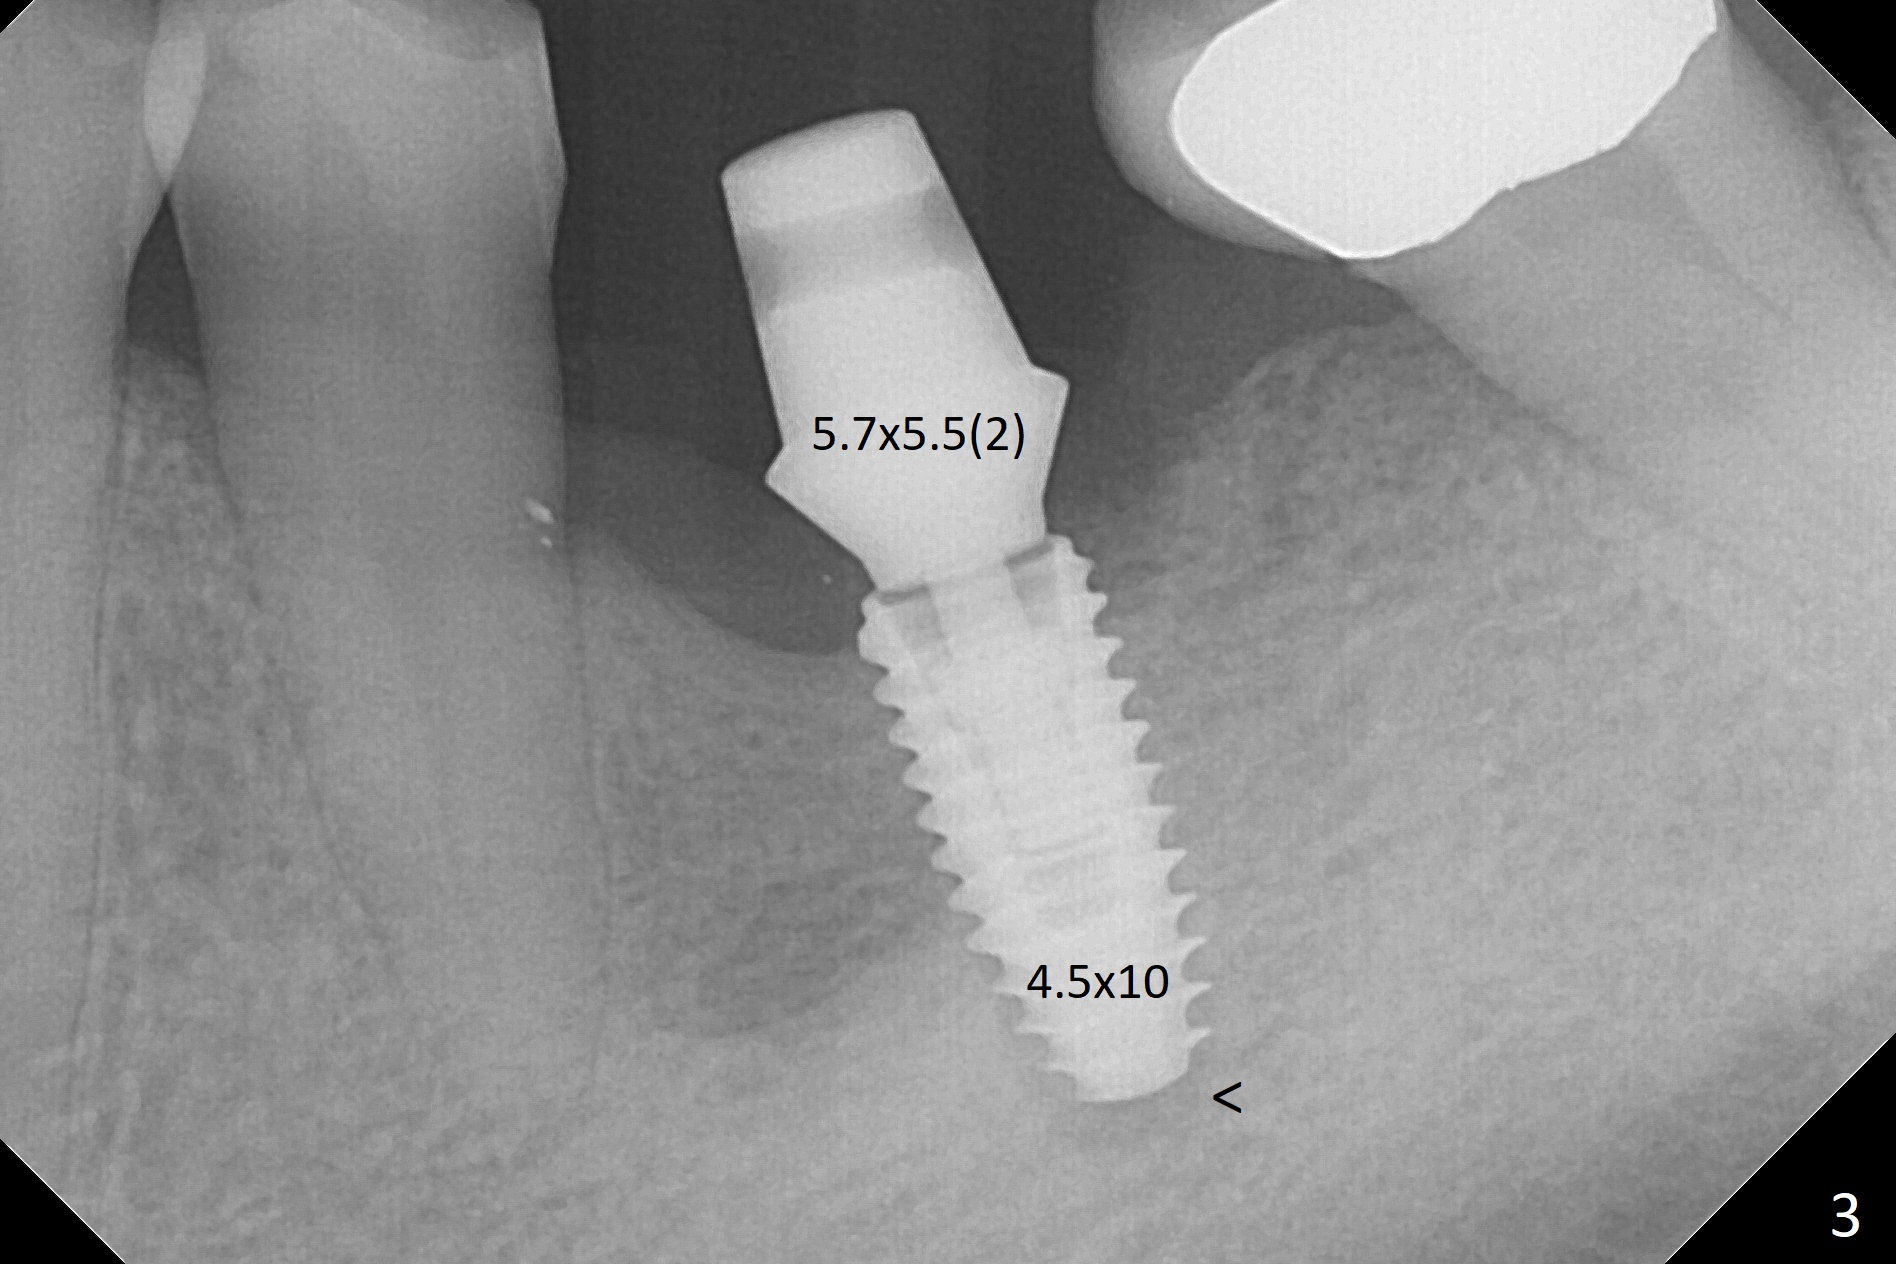

After extraction of the distal residual root at #19 (Fig.1), osteotomy is initiated in the mesial (M) aspect of the distal socket (Fig.2). Magic Split proves dense bone. When a 4.5x10 mm dummy implant is placed with stability, there is an apical space (Fig.3 <); the dummy abutment is 5.7x5.5(2). With the final implant (4.5x10 mm, Fig.4) being placed deeper to close the apical space, the cuff of the final abutment increases by 1 mm. Autogenous bone is used to pack around the implant distobuccally (*). Although the implant seems to be placed significantly apical to the lingual crest (^), it is at the buccal crest. There seems to be no bone loss 3 months postop; impression is taken (Fig.5). The crown/abutment at #30 is retightened 22 days post cementation (5 months postop), probably related to unilateral mastication. In fact, #30 is the only functioning molar on the right side (with unfavorable crown/implant ratio (long cuff 4 mm, vs. 3 mm at #19); #2 severely decayed); the crown at #19 is cemented at the same appointment (Fig.6). The crowns/abutments at #19 and 30 are loose 7 months later. When the crown/abutment at #30 is loose 2nd time 1 year 7 months post cementation, the screw at #19 fractures (Fig.7 taken post retightening). The tooth #2 needs a crown. The patient cannot use the anterior teeth, since the teeth #8 and 9 have root fracture. Can extraction and bone graft increase bone height? The abutment remains incompletely seated 9 months post screw replacement. It should be fixed soon. Return to Lower Molar Immediate Implant, Prevent Molar Periimplantitis (Protocols, Table), Armaments Screw Xin Wei, DDS, PhD, MS 1st edition 12/22/2017, last revision 02/24/2021